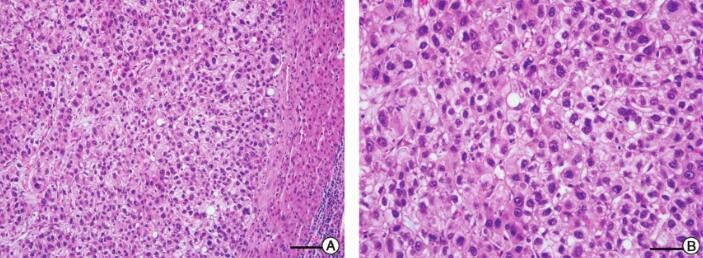

【病理结果】

取材部位:右肝叶组织。

HE及免疫组化染色:所检肝脏组织肝硬化不明显,呈现为肝炎后肝癌表现,癌细胞呈多边形,细胞质嗜酸性,细胞核圆形,以梁索状排列为主,梁索之间衬覆血窦,免疫组化染色见CD-34(+),CK8(++),Hepatocyte(+),Ki-67(+)(图4)。临床病理诊断:肝细胞癌(hepatocellular carcinoma,HCC)。

图4 患者右肝叶组织病理学检查结果

注:A.所检肝脏组织肝硬化不明显,呈现为肝炎后肝癌表现(10μm);B.癌细胞呈多边形,细胞质嗜酸性,细胞核圆形,以梁索状排列为主,梁索之间衬覆血窦(50μm);C~F.免疫组化染色CD-34(+)(50μm),CK8(++)(50μm),Hepatocyte(+)(100μm),Ki-67(+)(50μm)